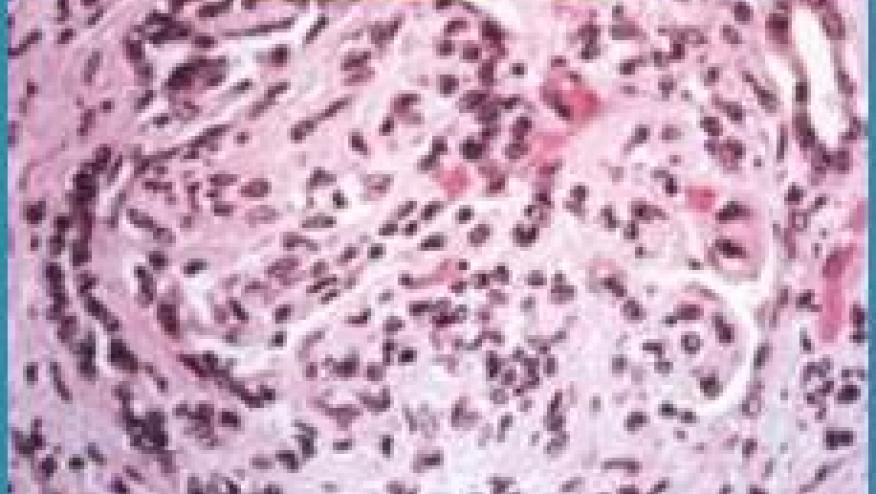

This trial set out to assess the efficacy and safety of oral mizoribine vs intravenous cyclophosphamide as induction therapy for Chinese patients with lupus nephritis. This prospective, multicenter, open-label, phase 3 randomized clinical trial recruited adult lupus patients with class III, III+V, IV, IV+V, or V lupus nephritis with 24-hour urinary protein levels greater than 1.0 gram/day and and a systemic lupus erythematosus disease activity index (SLEDAI) of 8 or higher. The primary endpoint was total remission rate (complete remission rate plus partial remission rate) after 52 weeks.